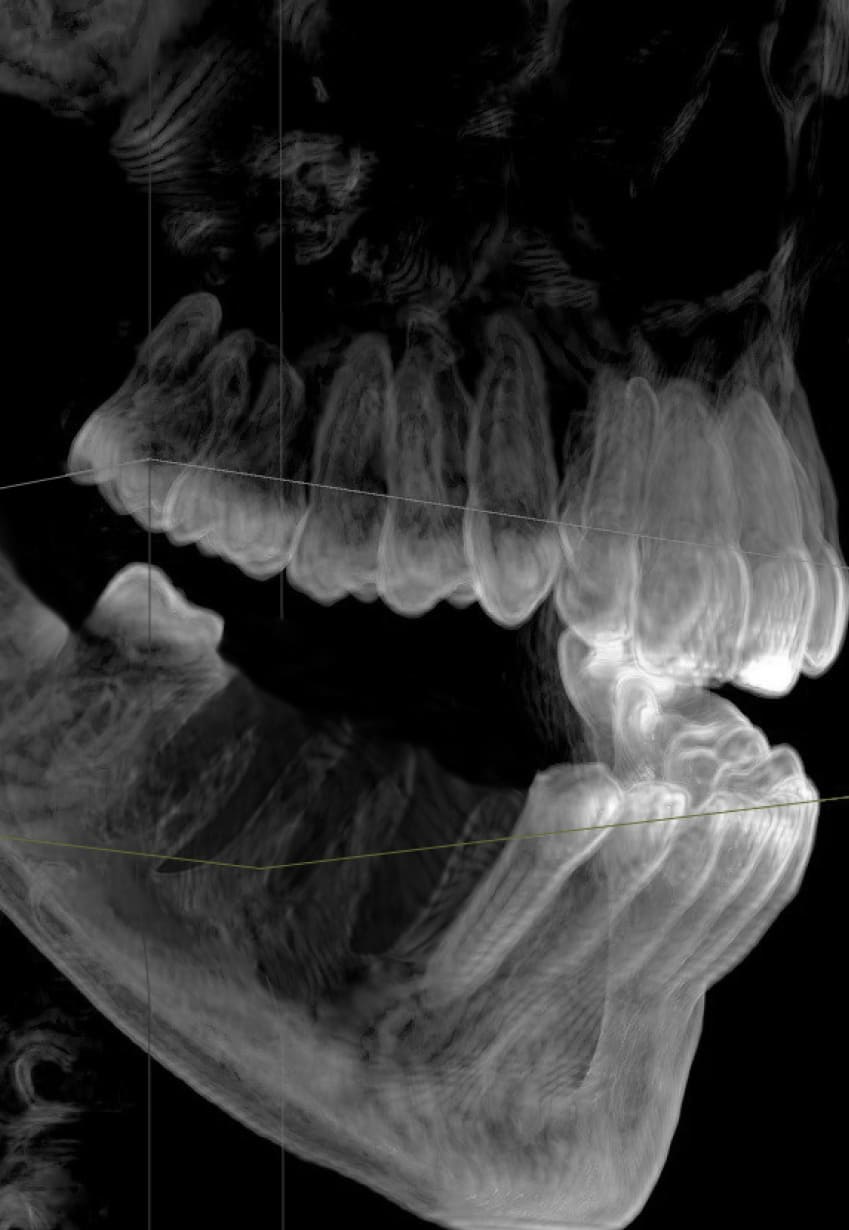

По 3D-модели врач определит положение будущих имплантов и составит план операции. В этом поможет искусственный интеллект, обученный на 50 000 случаев.

Ортопед изучит снимки и состояние вашего здоровья. Назначит консультацию с профильными специалистами.

Консультация и план

Комплексная 3D диагностика

Осмотр имплантолога и ортопеда